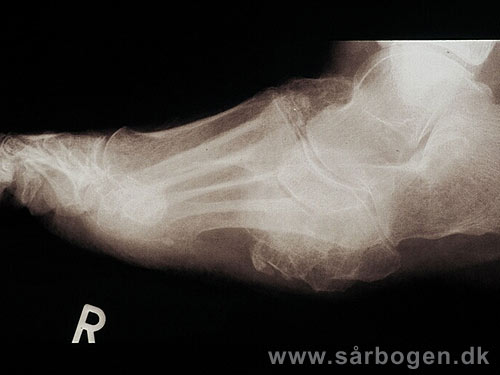

Charcot i mellemfod

Zoom

Charcot i mellemfod ...